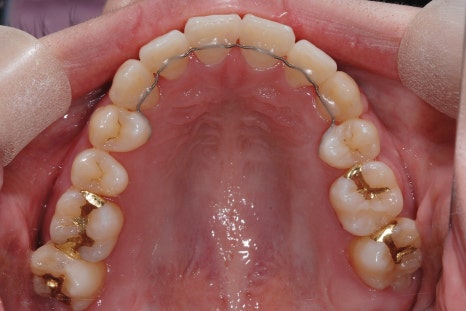

< 스마일디 치과 비발치 before & after >

*치료 전후 사진은 환자의 동의하에 게재하였으며, 동일한 환경과 조건에서 촬영된 전후 사진입니다.

어금니 후방 이동

가장 뒤쪽 어금니를 사랑니 공간 쪽으로 미세하게 밀어내어,

전체 치열이 뒤로 이동하며 공간을 확보하는 방법입니다.